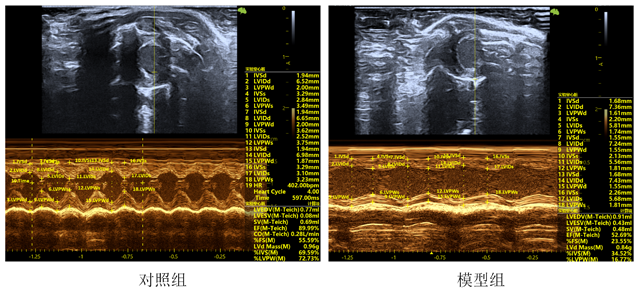

超声心动图

超声指标